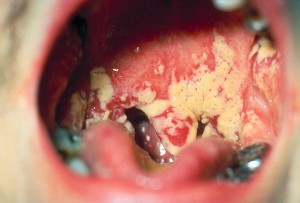

Клиническая картина. Характеризуется появлением рыхлого белого, легко снимающегося налета, рассеянного в начале заболевания на неизменной слизистой оболочке в виде отдельных точечных очагов, напоминающих свернутое молоко. Затем, сливаясь, эти очаги могут распространяться по всей слизистой оболочке полости рта в виде сплошного налета, который состоит из мицелия и спор гриба, отторгнутого эпителия, лейкоцитов и бактерий.

В запущенных случаях удаление налета сопряжено с травмой слизистой оболочки, так как мицелий, прорастающий поверхностные слои эпителия, в дальнейшем проникает в более глубокие слои.